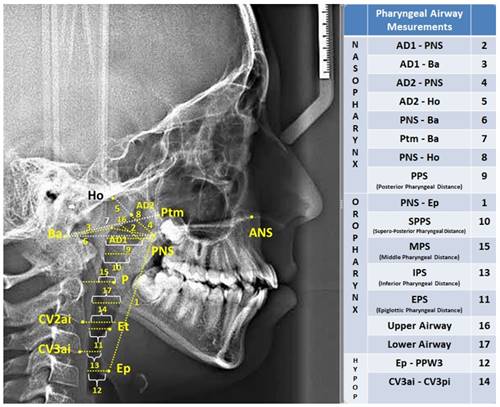

Lateral cephalometric films included in the study were calibrated on the Planmeca Romexis (Planmeca Romexis Viewer®, Helsinki, Finland) software program and were printed on tracing paper in 1:1 dimension in real size. Then, measurements were made by drawing the following cephalometric points and planes with the help of a 0.3 mm lead pencil. The cephalometric landmarks used in the study are shown in Figure 1, pharyngeal airway measurements in Figure 2, and hyoid measurements in Figure 3.

Area measurements were performed on digital lateral cephalometric films after digital calibration was performed in SketchAndCalc™ software program (SketchAndCalc Area Calculator software, Axiom Welldone ©, https://www.sketchandcalc.com/ . Area measurements are shown in Figure 3.

Figure 2

| Figure 2 Pharyngeal Airway Measurements |

When the effects of growth and development periods on the pharyngeal airway are examined, the differences between the pre-peak group and the peak group in the nasopharynx are AD1-PNS (mm), AD2-PNS (mm), PNS-Ba(mm), Ptm-Ba(mm), PNS-Ho (mm), posterior pharyngeal length (PPS) and upper airway measurements defined by McNamara were statistically significant (p<0.05). A statistically significant difference was found between the pre-peak group and the post-peak group in all measurements in the nasopharynx (p<0.05). A statistically significant difference was found between the pre-peak group and the post-peak group in AD1-PNS (mm), AD2-PNS (mm), AD1-Ba(mm), AD2-Ho(mm) and posterior pharyngeal length (p<0.05) Table 2.

In the oropharynx part of the airway measurements, a statistically significant difference was found only in the vertical airway length PNS-Ep(mm) between the pre-peak group and the peak group (p<0.05). A statistically significant difference was found between the pre-peak group and the post-peak group in PNS-Ep(mm), upper posterior airway length (SPPS), epiglottic airway length (EPS), and lower pharyngeal length (IPS) (p<0.05). A statistically significant difference was found between the pre-peak group and the post-peak group in PNS-Ep(mm) and lower pharyngeal length (IPS) (p<0.05) Table 2.